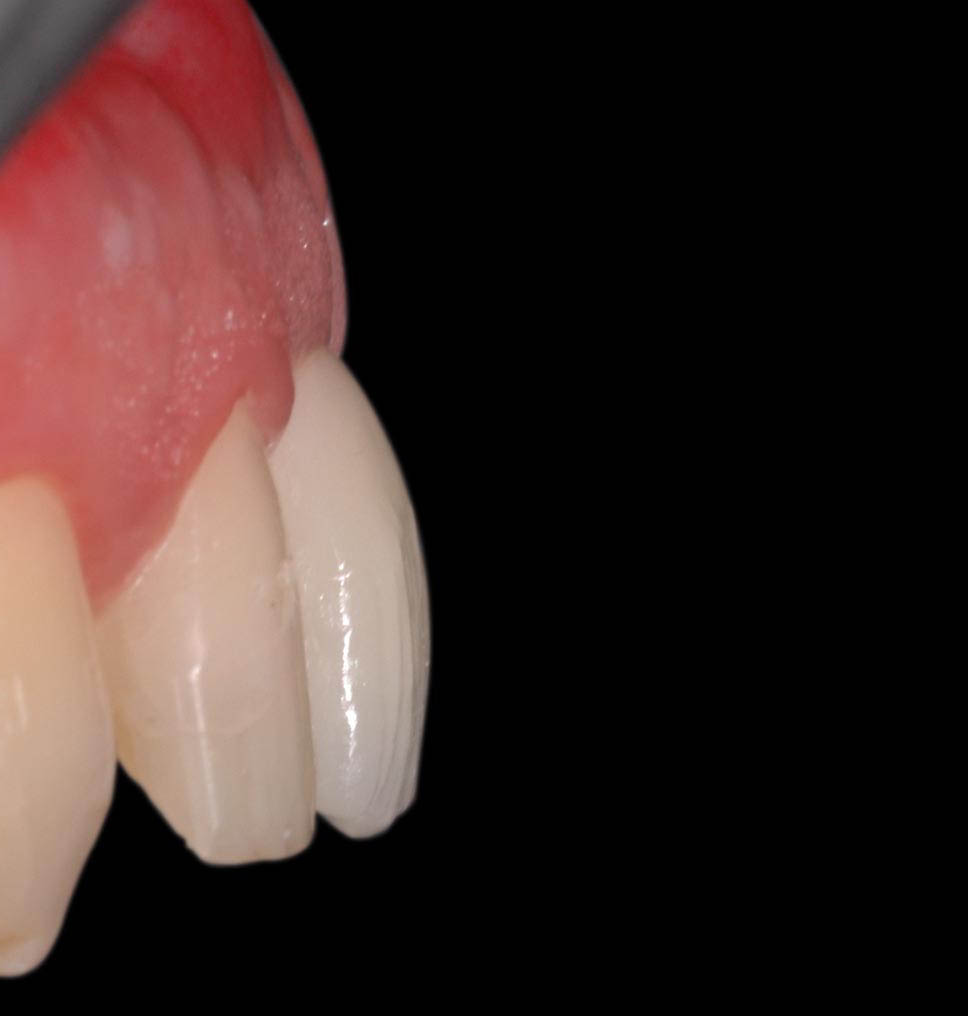

Definitive crown in lithium disilicate, cemented with resin cement.

Detail of the healing of the tissues.